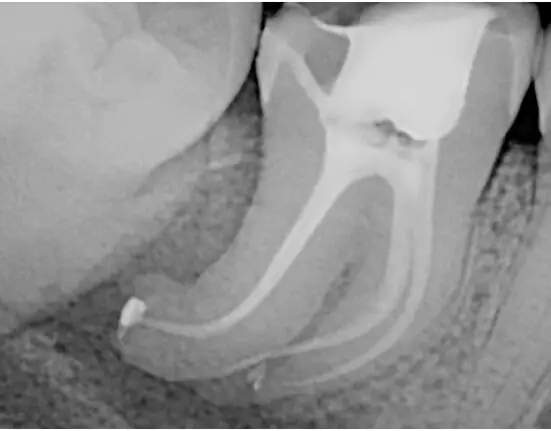

A patient came in with pain and slight numbness on the lower right side. I took a 2-D panoramic X-ray of tooth No. 31 (Figure 1). It was obvious that there was a lesion present, but it was difficult to see its proximity to the inferior alveolar nerve bundle (IANB).

Pulp testing revealed a necrotic pulp with acute apical periodontitis. I then took a large field-of-view CBCT to observe the size and location of the pathology to the IANB and the root canal anatomy (Figures 2 and 3). The periapical pathology (PAP) was very extensive, sitting very close to the IANB on the CBCT (Figures 3 and 4).

I performed endodontic treatment in one visit (Figures 5 and 6). Notice the severe curvature of the canals. I used heat-treated NiTi files on this case with bioceramic sealer. The heat-treated NiTi files are very strong and flexible, which minimizes file separation. The bioceramic sealer acts like calcium hydroxide and liquid MTA to promote healing. It’s a great seal, too.

The patient was asymptomatic and the numbness was relieved after one week.